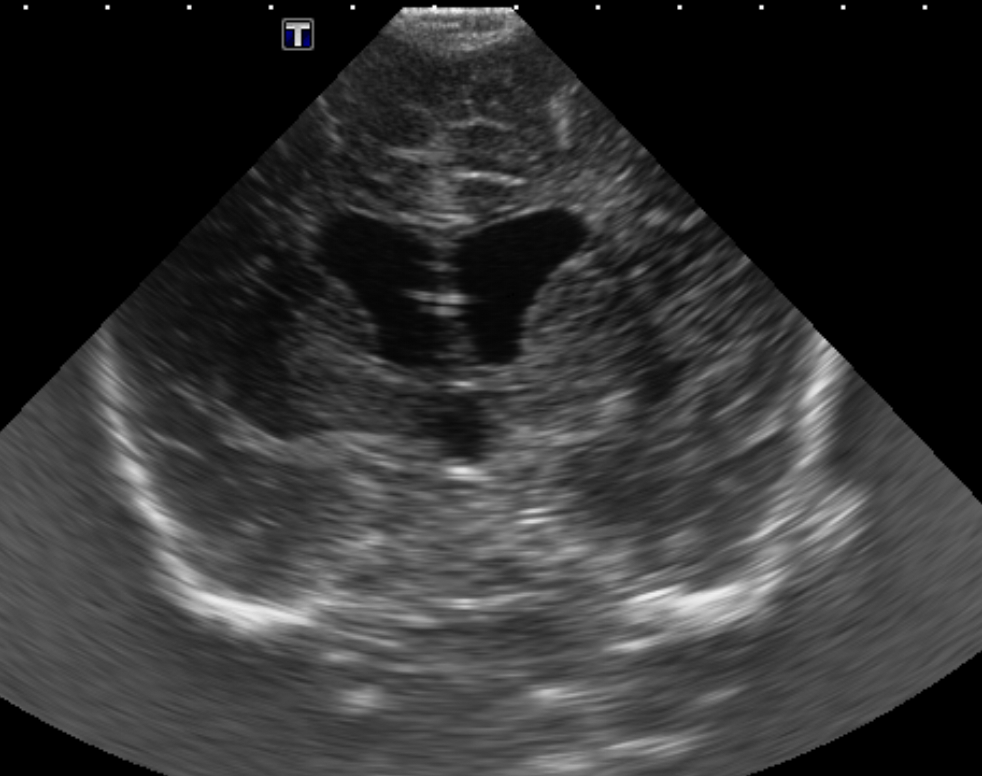

Info Images Findings Impression Reco/Acuity Case Images View Images / Launch Visage Case Notes History Full term infant. We are asked to evaluate posterior fossa cyst. Exam Gray scale and Doppler Ultrasonographic examination of the head. Prior Study N/A Dicom View Reference Material

Section 1 Submit Findings Case149 Findings Brain The brain is immature. Yes No There is under-sulcation and open sylvian fissures. Yes No There is/are multiple hypoechoic areas in the periventricular white matter. Yes No There is/are multiple hyperechoic areas in the periventricular white matter. Yes No There is diffuse cerebral edema with diffusely increased echogenicity of the brain parenchyma and loss of grey white matter differentiation. Yes No The thalami/basal ganglia are hypoechoic. Yes No There is periventricular calcification. Yes No There is intra-parenchymal calcification. Yes No CSF spaces/ventricular system There is a prominence of the extra axial fluid spaces. Yes No There are debris/septations in the extra axial fluid spaces. Yes No There are debris/septations in the ventricles. Yes No There is a subdural collection on the right/left side. Yes No There is prominence of the ventricular system. Yes No There is an asymmetry of the ventricular system. Yes No There is a cavum septum pellucidum. Yes No There is a midline shift towards right/left. Yes No The choroid plexus is bulky/lobulated. Yes No There is a choroid plexus cyst measuring… Yes No There are debris/clots in the occipital horn. Yes No There is a posterior fossa cyst measuring… Yes No The tentorium is elevated/depressed. Yes No The lateral ventricle/s are dilated. Yes No The third ventricle is dilated. Yes No The 4th ventricle is dilated. Yes No There are pseudo cysts. Yes No Germinal matrix hemorrhage (Only in the premature infants): Please do not answer if the patient is a full term. There is a germinal matrix hemorrhage, consistent with a grade I hemorrhage. Yes No There is an intraventricular extension consistent with a grade II hemorrhage. Yes No There is an intraventricular extension with the dilatation of ventricles, consistent with a grade III hemorrhage. Yes No There is an intra-parenchymal extension, consistent with grade IV hemorrhage. Yes No On color Doppler examination, the Resistive index in the anterior cerebral artery is… There is a loss of the diastolic flow on the Doppler exam. Yes No There is altered vascularity on Doppler imaging. Yes No There is an AVM in the region of… Yes No